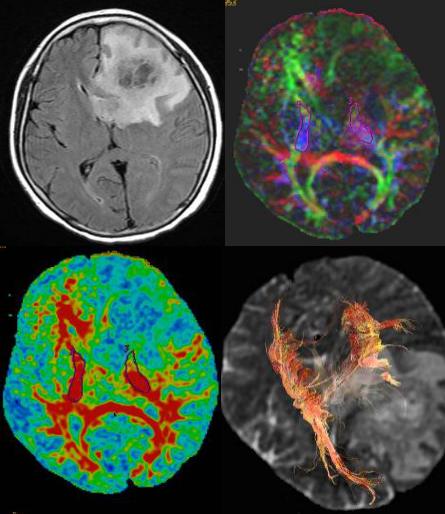

DTI也可显示血肿、梗死区与纤维束的关系,如接近、穿行、中断等,有助于判断白质纤维束损害程度与身体相应部位的功能障碍的关系,有助于判断临床治疗效果、判断病人恢复、预后。

右侧基底区急性期梗死FA值下降,纤维束局部中断